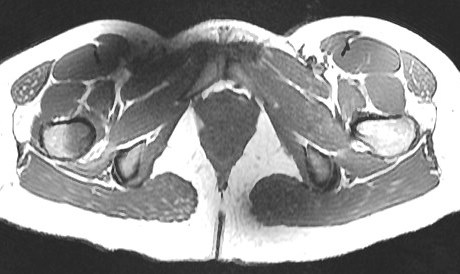

Figure 1 for case Calcar stress fracture ( RID4695 )

Figure 1